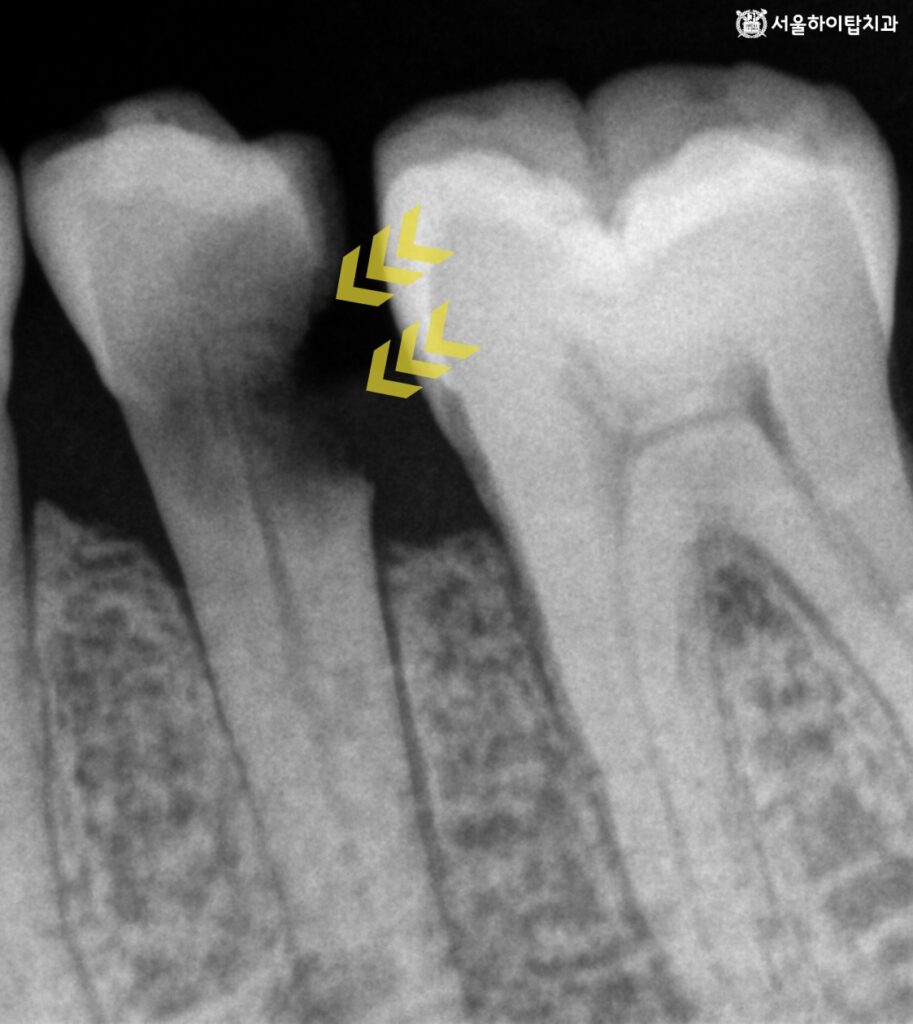

대략 2년 정도가 흐른 뒤 촬영된 PA 사진을 보면

이미 치수를 침범하여 병소의 크기가 상당히

넓어진 모습을 확인할 수 있습니다.

여기에 더해, 간석오거리역 치과 에서는

치수가 괴사하였을 때 나타나는 치아 변색까지 뚜렷하게 확인할 수 있습니다.